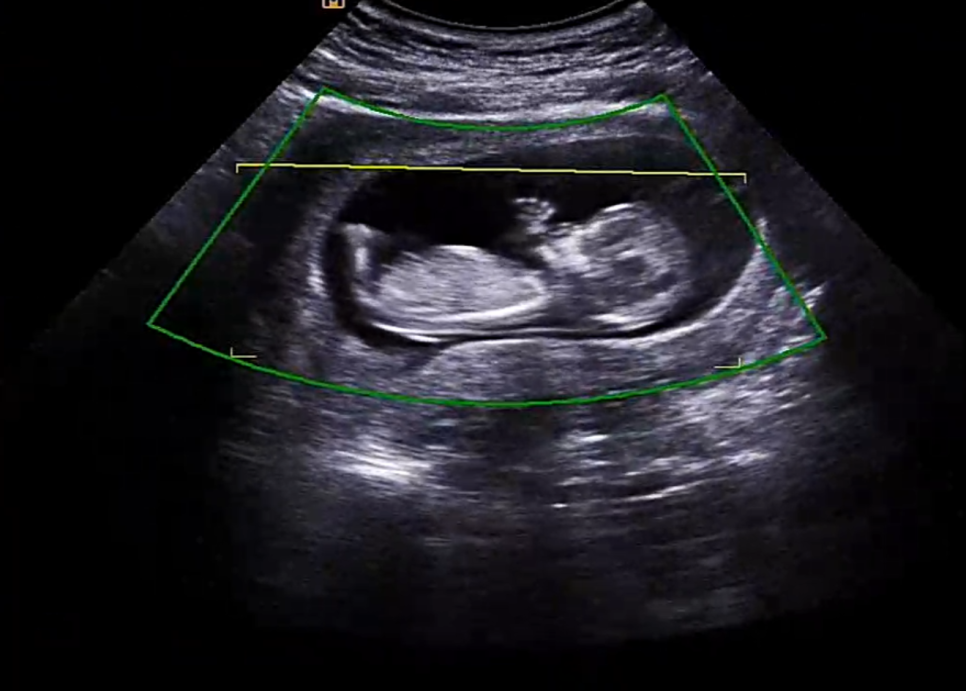

검사 중 킥 실력을 자랑하는 오뜨ㅋㅋ

초음파로 어떤 걸 보는지 검사 리뷰 같은 걸 공유해볼게요 ~^^

우선 1차기형아검사 초음파에서 제일 먼저 확인했던 머리~꼬리뼈의 길이 ㅎㅎ #임신 12주차 정도가 되면 6~7cm 정도가 된다고 합니다. ^^

안녕하세요~~해주는 오토 그리고 또 코가 잘 자라는지 확인하는데 이것도 다운증후군과 관계가 있다고 하네요.다행히 코뼈도 멋있네요.손가락도 딱 다섯개 ㅎㅎ 이미 뼈가 생겼어요! 손으로 안녕~ 하고 인사하는 것 같다고 남편이랑 두근두근하고 있어…ㅋㅋㅋㅋㅋㅋㅋ

1차 기형아 검사 중 #12주성별도 한번 봤는데 다리 사이에 뭔가 봉긋한 것이 존재감 뿜뿜이네요? 그런데 혹시 아들이세요? 그러면 탯줄일수도 있고, 손일수도 있고, 그게 없어질수도 있다고 ㅎㅎ 16주가 지나서 보는게 가장 정확하다고 했어요!아들이든 딸이든 건강했으면 좋겠어요^^!

심장 박동도 확인해주시고요153비트가 나왔는데 정상이라고 하더라고요.

이렇게 오늘은 1차 기형아 검사 후기를 써봤습니다#1. 차기형 검사 결과는 다행히 문제가 없었습니다 초음파로는 뇌 발달, 콧날이 발달했는지, 목구멍 투명대 검사, 아기의 크기, 심장 박동 정도를 보는 것 같습니다. 입체 초음파 사진도 찍어주세요~